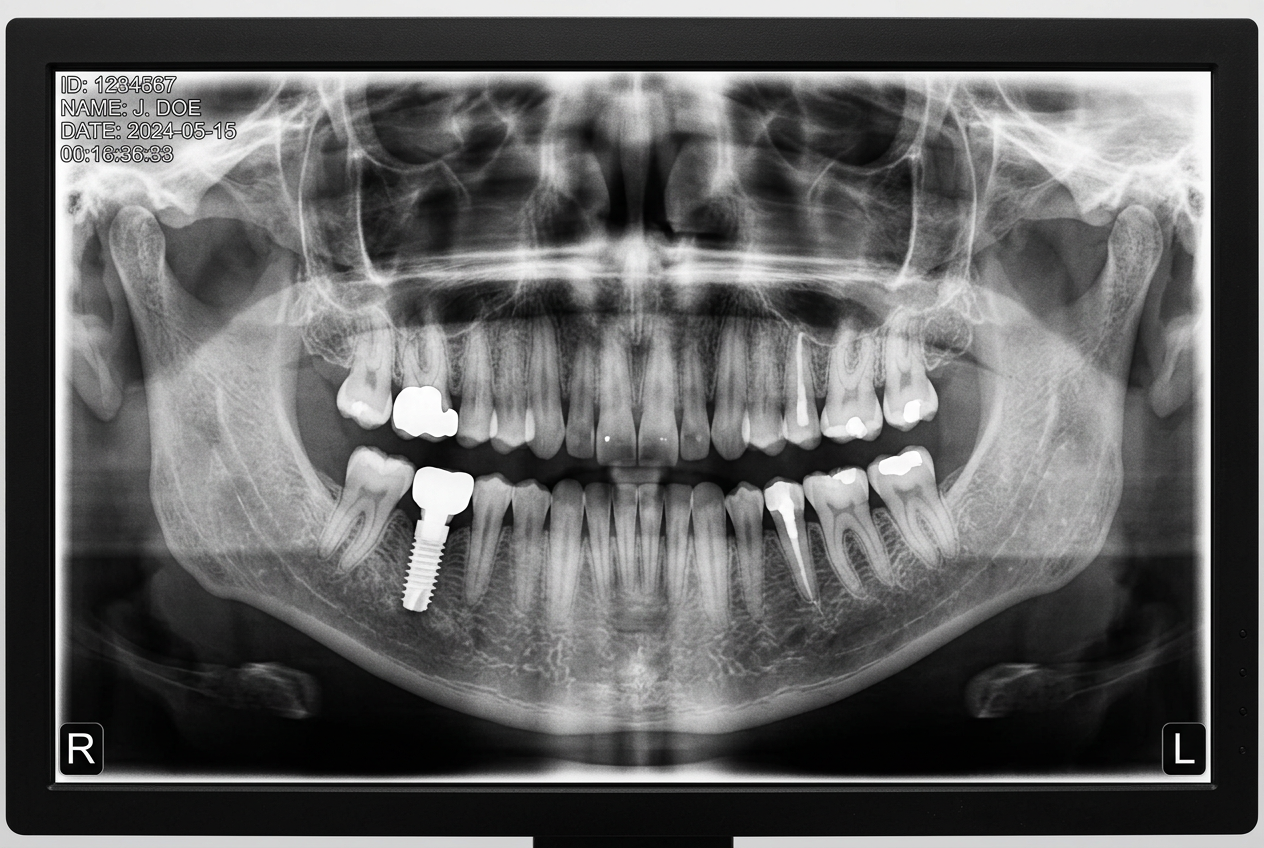

Recentemente utiliza-se este material no fabrico de implante dentário. Destaca-se pelas óptimas propriedades mecânicas e biológicas. Trata-se de uma matéria prima sem toxicidade e o risco de alergia é quase nulo.

Recentemente surgiram os de cerâmica, nomeadamente zircónio.

Ao contrário dos de titânio que são compostos por duas peças, implante e pilar, os de zircónio são uma peça única. Por se tratarem de uma única peça a estabilidade da prótese pode aumentar.